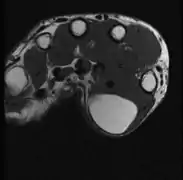

A physical exam is typically the easiest way to diagnose it. Rarely, a tissue biopsy or imaging may be required. The imaging modality of choice is magnetic resonance imaging (MRI) because it has superior sensitivity of distinguishing it from liposarcoma as well as mapping the surrounding anatomy.[22]

- Medical ultrasonography of a lipoma in the thenar eminence: It is hyperechoic compared to adjacent muscle, and relatively well-defined, with miniature hyperechoic lines.[23]

- Ultrasonography of a liposarcoma for comparison: In this case a heterogeneous mass consisting of an upper hyperechoic portion, corresponding to lipomatous matrix, and areas of hypoechogenicity corresponding to nonlipomatous components.[24]

- Ultrasonography of a liposarcoma mimicking lipoma. A homogeneous hypoechoic mass presenting with the same appearance of lipoma. It was clinically distinguished by having rapid growth.[24]

- MRI showing lipoma of the arm